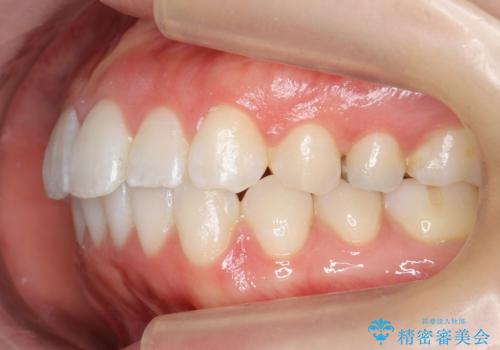

前歯のがたつき インビザラインで

治療症例の内容

- 前歯のがたつきを治したいとのことでした。歯を抜かずにできる範囲で引っ込めたいとのことでした。

歯列の側方拡大(横に広げる)と、エナメル質の削合で並べました。

歯を抜いているわけではないので、口元はそこまで変化はありませんが、前に出すことなくデコボコは取れたと思います。